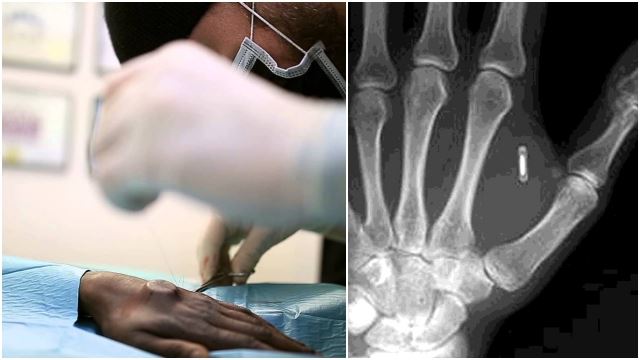

Syarikat di UK Tanam Cip Mikro Dalam Badan Pekerja Ganti Kad ID